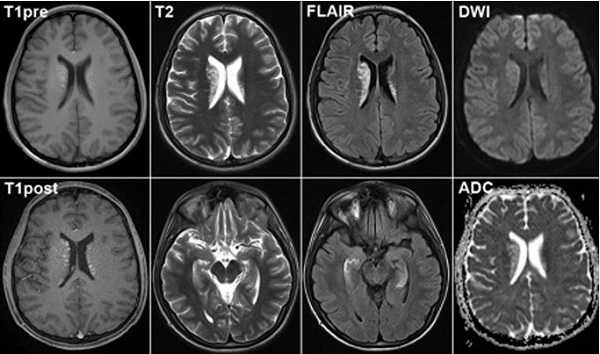

Диффузно-взвешенное изображение.

DWI наиболее чувствительна к инсульту. В результате цитотоксического отека возникает дисбаланс внеклеточной воды к Броуновскому движению, поэтому данные изменения выявляются отлично на DWI. В норме протоны воды диффундируют внеклеточно, поэтому теряется сигнал. Высокая интенсивность сигнала на DWI указывает на ограничение протонов воды диффундировать внеклеточно.

Представлены ДВИ инфаркт передней, задней, средней мозговой артерии.

Когда мы сравниваем результаты на T2WI и DWI во времени, мы заметим следующее: В острой фазе T2WI норма, но со временем зона инфаркта станет гиперинтенсивной. Гиперинтенсивность на T2WI достигает своего максимума между 7 и 30 дней. После этого сигнал начинает угасать. На DWI гиперинтенсивная область в острой фазе, а затем становится более интенсивной с максимумом на 7 дней. На DWI у пациента с инфарктом головного мозга визуализируется гиперинтенсивная область примерно на 3 недели после начала заболевания (при инфаркте спинного мозга на DWI визуализируется гиперинтенсивная область на одну неделю!). На ADC будет сигнал низкой интенсивности с минимальной интенсивностью в первые 24 часа, после сигнал будет увеличиваться в интенсивности и, наконец, становится максимально интенсивным в хроническую стадию.